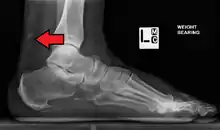

Magnetic resonance imaging may be useful to guide muscle biopsy and to investigate involvement of internal organs;[12] X-ray may be used to investigate joint involvement and calcifications.[13]